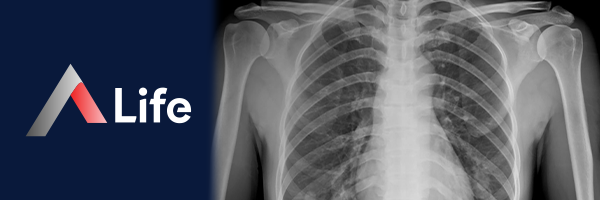

Akciğer Röntgeni​

Akciğer röntgeni, göğüs kafesinin, akciğerlerin, kalbin, büyük kan damarlarının ve diyaframın iç yapısını görüntülemek için kullanılan yaygın bir tanısal görüntüleme yöntemidir. Bu işlem, göğüs bölgesinden X-ışınları geçirilerek ve bu ışınların bir film veya dijital dedektör üzerine düşürülmesiyle gerçekleştirilir. X-ışınları, kemikler ve organlar gibi yoğun yapılar tarafından emilirken, daha az yoğun dokulara (akciğerler gibi) geçebilir. Bu, akciğerlerin ve diğer yapıların detaylı görüntülenmesini sağlar.

Akciğer Röntgeni Ne İçin Kullanılır?

Akciğer röntgeni, birçok farklı amaç için kullanılabilir: